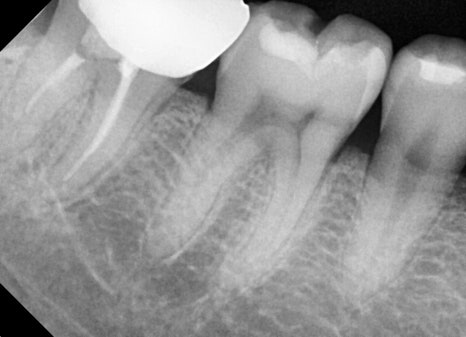

Through panoramic X-ray imaging,

we confirmed that a deep cavity had progressed in the first molar on the lower right (first molar).

Fortunately, it had not reached the nerve, so the tooth could be saved with inlay treatment

without root canal treatment.